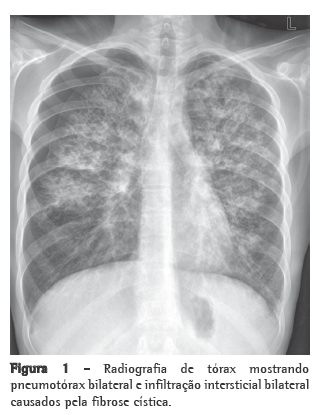

No entanto, a radiografia de tórax mostrava obliteração do seio costofrênico direito. O estudo tomográfico de tórax confirmou a presença de derrame pleural associado a uma área de consolidação (Figura 1). A avaliação do serviço de cirurgia torácica indicou a realização de toracocentese pela suspeita diagnóstica de derrame parapneumônico. A punção pleural revelou a presença inequívoca de um hemotórax. Mediante este achado, foi proposta a exploração do espaço pleural através de videotoracoscopia, que identificou hemotórax de moderadas proporções (aproximadamente 500 mL) junto à goteira paravertebral. Após a aspiração do conteúdo sangüíneo, foi possível a visualização de uma área de aspecto hepatizado, sem contato com o pulmão.